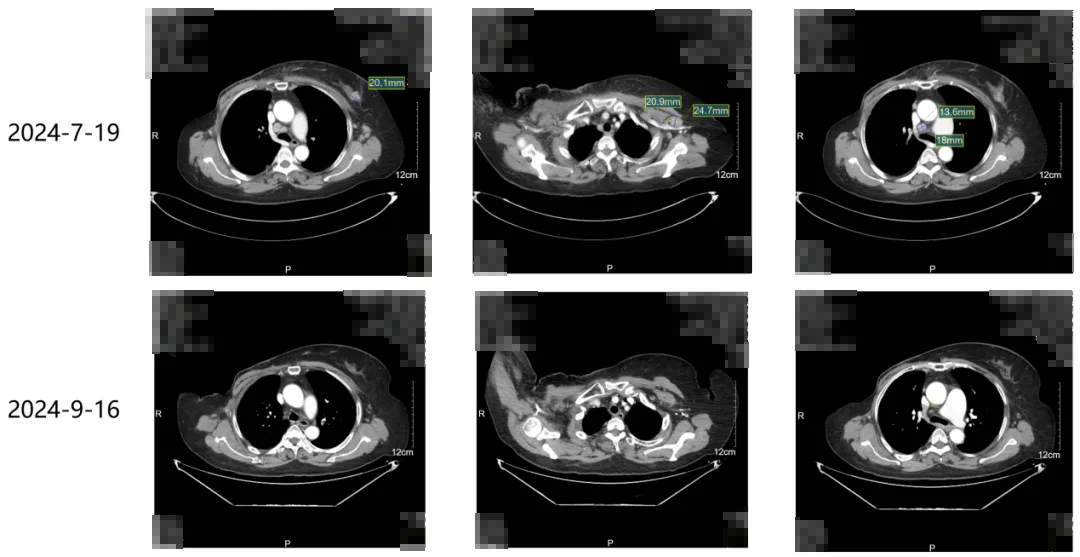

一线治疗:艾立布林+伊尼妥单抗+吡咯替尼3次,疗效PR。

·2024年9月16日本院随访

本病例是一例经过THP新辅助治疗之后non-pCR的HER2阳性乳腺癌患者,手术后经过辅助化疗、辅助放疗以及长期的HP双靶辅助治疗,达到26个月的DFS;患者在辅助治疗9个月后复发。

在经过对EMERALD研究以及真实世界临床研究进行评估后,由于艾立布林较紫杉类的耐受性表现更好,为了给患者争取更长时间的生存获益,我们对患者采用了艾立布林+伊尼妥单抗+吡咯替尼一线治疗方案,并取得了PR的控制效果,为抗HER2治疗带来了新的思路。